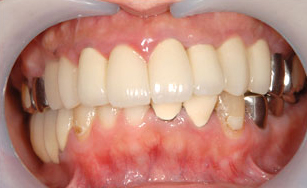

インプラント・

メタルボンドの症例

| 年齢・性別 | 54歳・男性 |

| 治療期間 | 6ヶ月 |

| 治療内容 | インプラント・メタルボンド・保険 |

| 治療本数 | 20本 |

| 治療費用 | インプラント(330,000円(税込)×4本) +メタルボンド(132,000円(税込)×6本) +保険治療 |

| 副作用等 | 外科手術により腫れが生じることがあります。 手術範囲や方法により異なりますが、 次第に腫れが引いてくることがほとんどです。 |